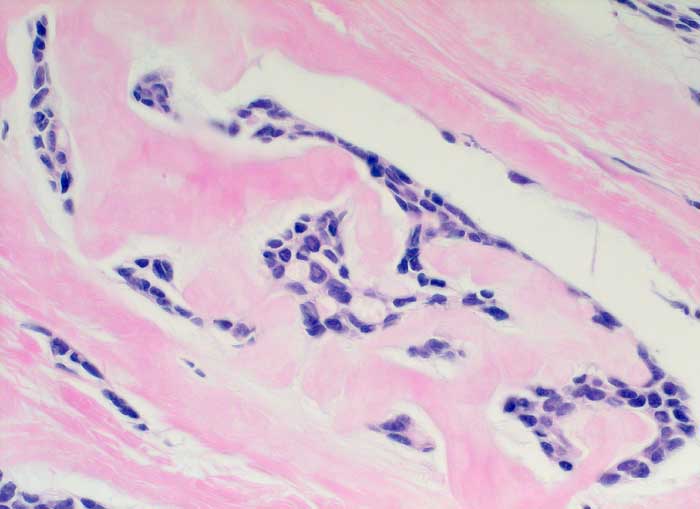

Adenoidzystisches Karzinom

maligner Tumor

Mamma

Dichtes amyloidartiges Stroma umschliesst residuelle zylindromatöse Knoten.

Adenoidzystische Karzinome kommen vor allem im Bereich der Speicheldrüsen vor, treten aber auch in anderen Organen auf. Sie machen weniger als 0.1% - 0.2% der Mammakarzinome aus.

Histologie

400